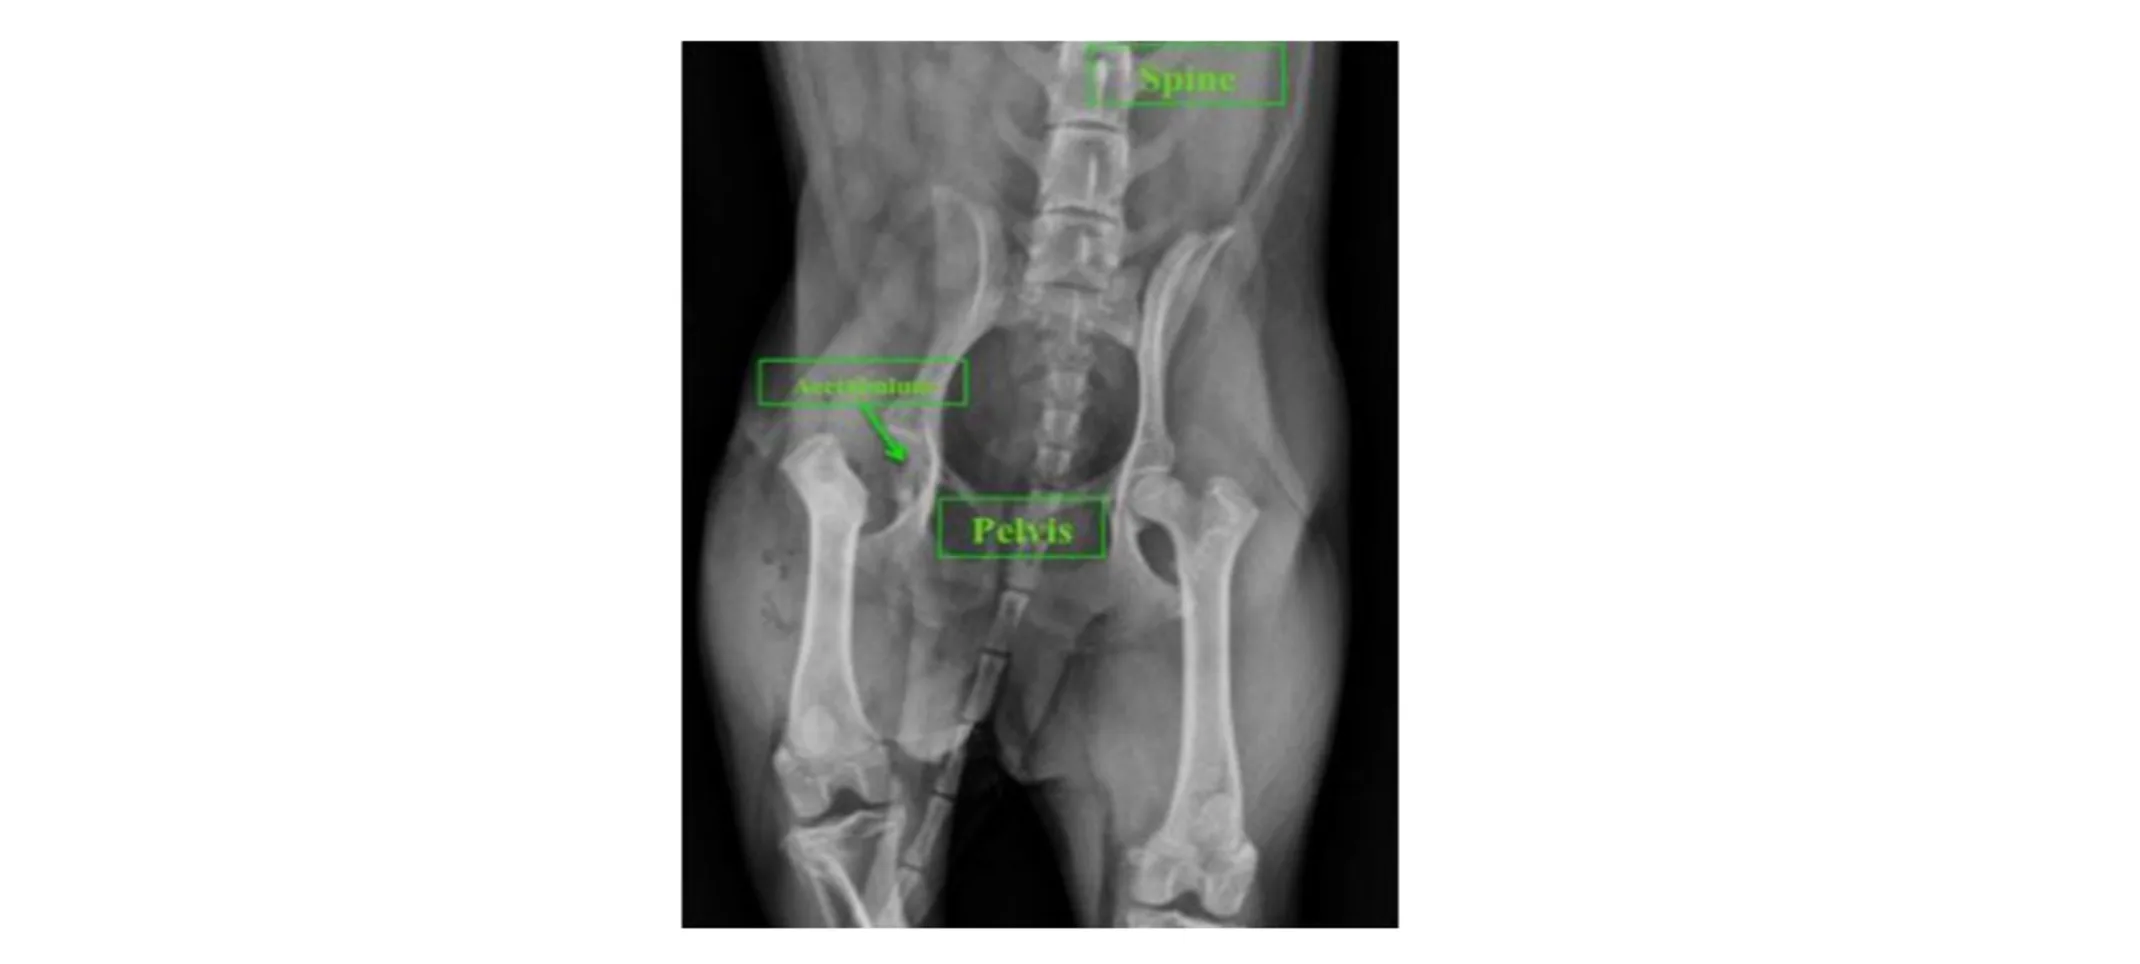

Diagnostic imaging such as radiography (X-rays) or CT may be used to determine the underlying cause of hip pain/lameness and potentially plan for surgical procedures that preserve the hip joint. The choice to perform an FHO is determined by the patient’s condition and discussion between the owner and veterinarian. Below is a radiograph of a patient suspected to have aseptic necrosis of the femoral head. Notice the difference in density and appearance between the left and right femoral head. An FHO was chosen for this patient.